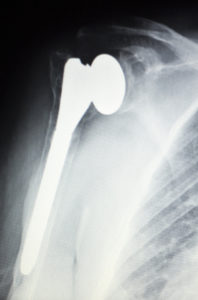

Shoulder Replacement Surgery: Traditional vs. Reverse

Shoulder replacement is the surgery of choice for more than 50,000 Americans every year. And it’s no wonder: this joint replacement procedure can effectively relieve chronic shoulder pain and improve range of motion. Patient satisfaction rates are 95% after a shoulder replacement surgery. If you [Read More]